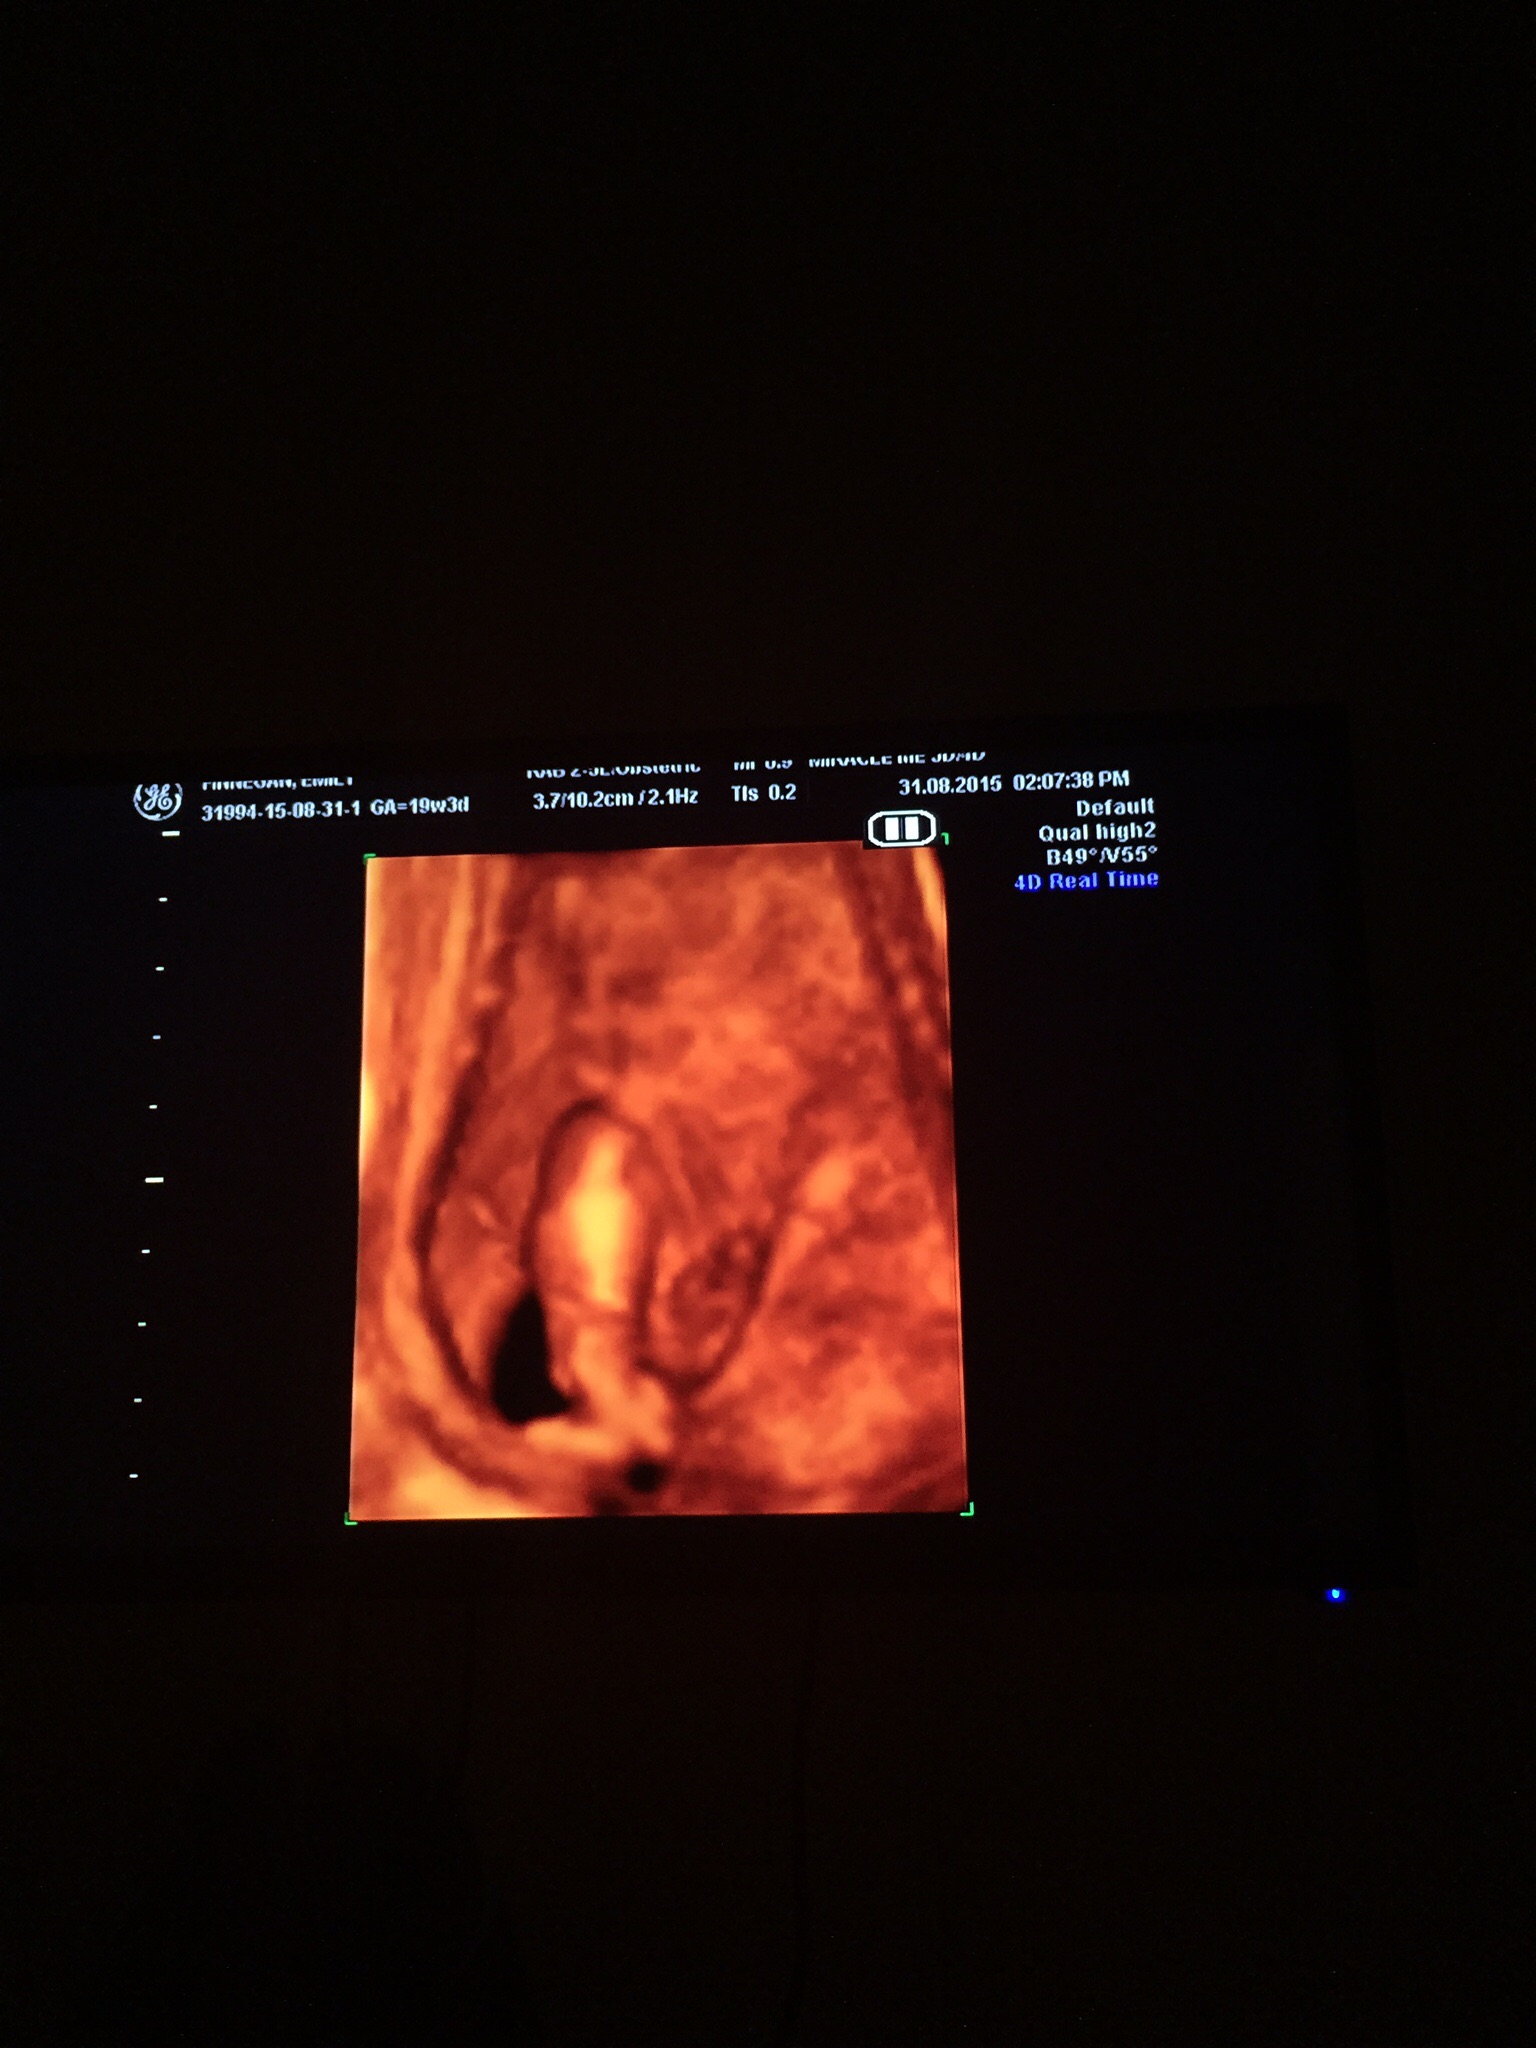

Attachment 27333These are 2d & 3/4 d scan pictures at 19 weeks 3 days any guesses?? Please? Attachment 27332

Boy parts in 4d

This is tricky. I say a very half way faded penis. It looks too long to be a girl.